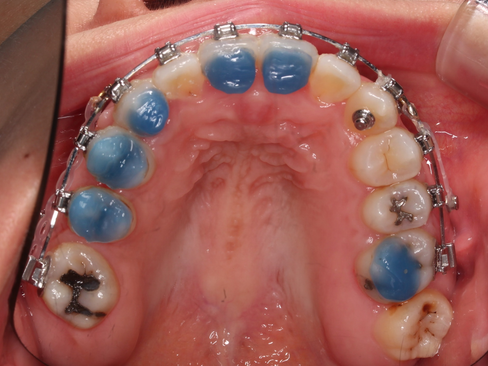

교정 중 안쪽 어금니 부위(씹는면)에 충치가 생겨있는 부위도 치료를 병행했습니다.

충치의 범위가 넓은 편이라 부분보철을 진행하였는데요.

여기서 사용한 재료가 세라믹 인레이 입니다.